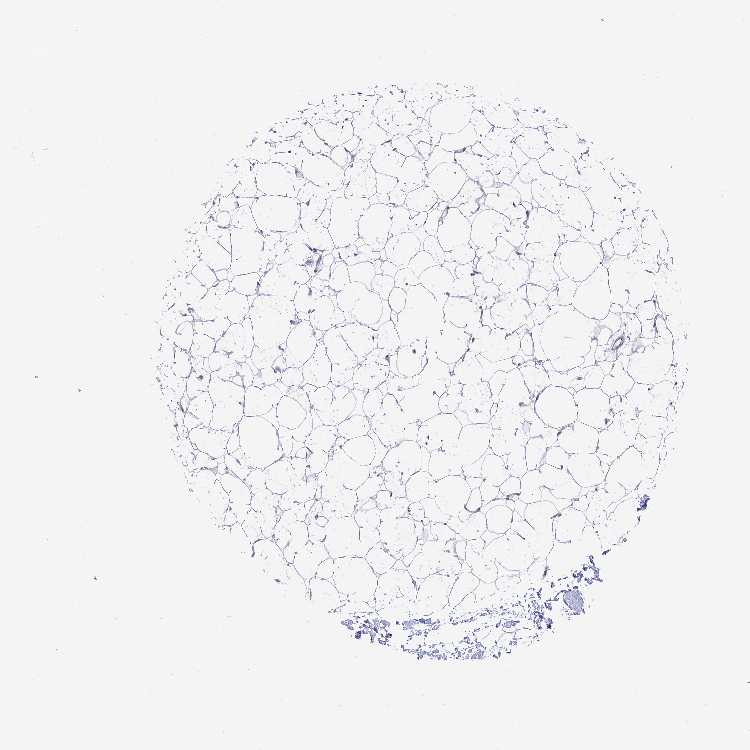

SOFT TISSUE 1 - Antibody stainingi

Antibody staining in the annotated cell types in the current human tissue is reported as not detected, low, medium, or high, based on conventional immunohistochemistry profiling in selected tissues. This score is based on the combination of the staining intensity and fraction of stained cells.

Each image is clickable and will lead to virtual microscopy that enables deeper exploration of all samples and also displays staining intensity scores, fraction scores and subcellular localization as well as patient and tissue information for each sample.

Antibody HPA035097Antibody CAB010753

Fibroblasts Not detectedLow

Peripheral nerve Not detectedLow

SOFT TISSUE 2 - Antibody stainingi

Fibroblasts Not detectedMedium

Peripheral nerve -Low